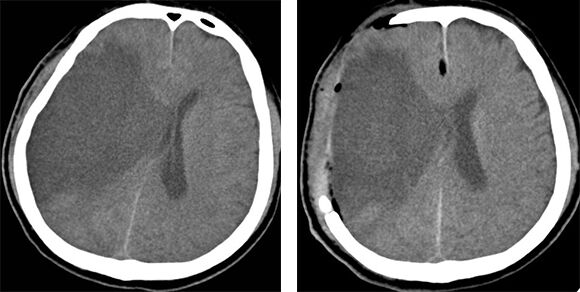

Đặc điểm lâm sàng, cận lâm sàng nhồi máu não cấp tại Bệnh viện Đa khoa trung tâm Tiền Giang

BÁO CÁO KHOA HỌC 52